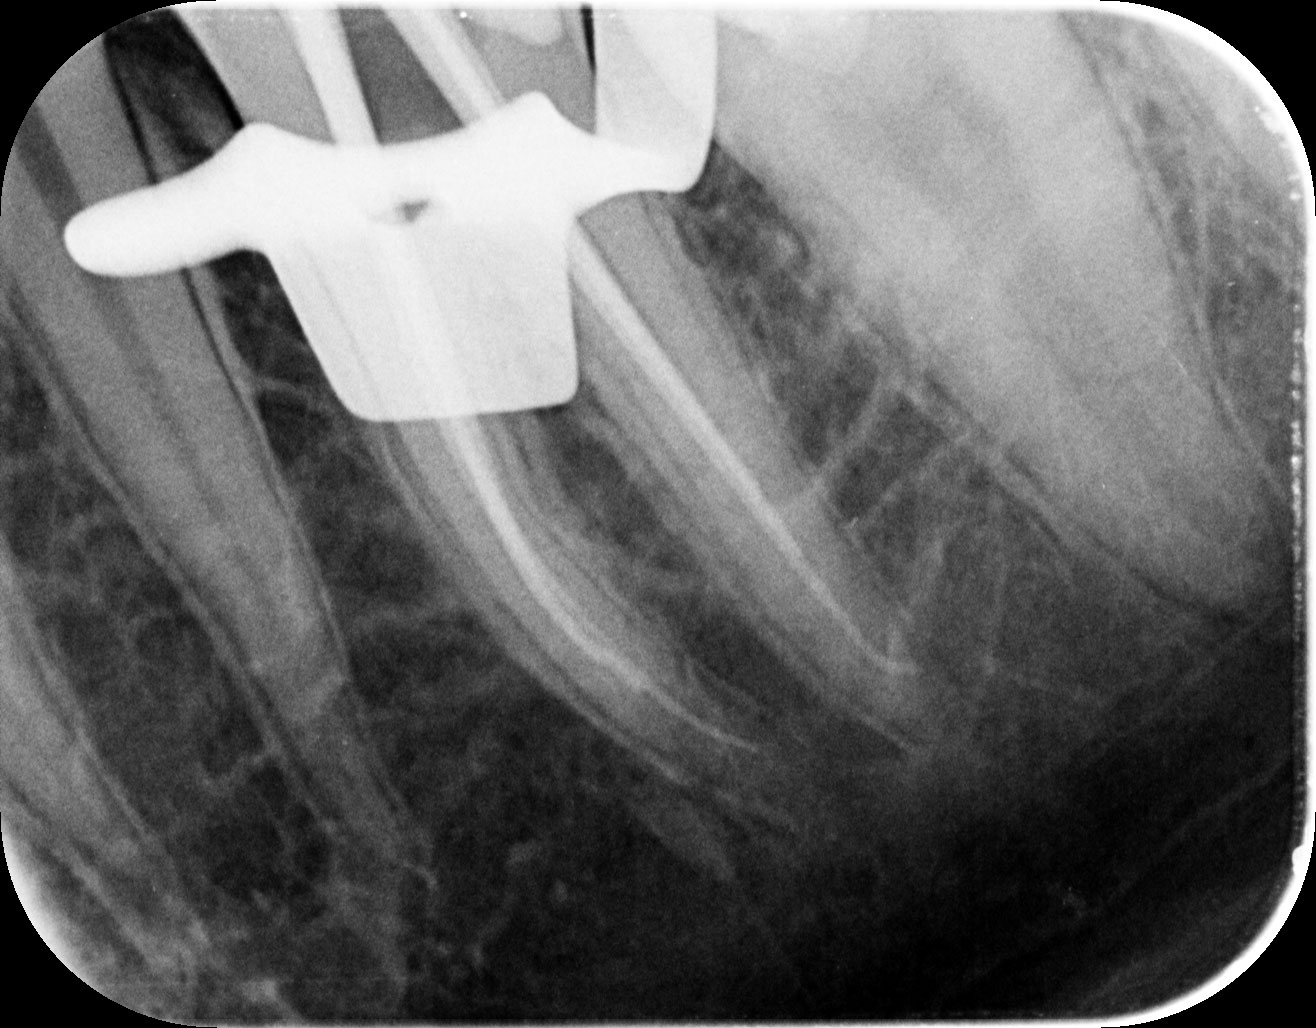

Besimptominė pulpos nekrozė, išsivalius seną plombą bei antrinį kariesą, atsivėrė pulpos ragelis, viduje nekrozė, todėl toliau atlikome endodontinį gydymą.